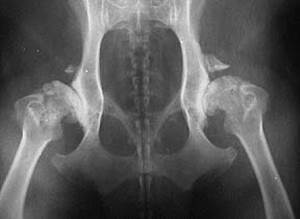

Генетические нарушения строения могут быть не только одной конкретной разновидности, но и несколько одновременно, накладывающихся друг на друга. По наиболее часто используемой схеме все имеющиеся отклонения суммируются, и по сумме баллов определяется степень дисплазии. Наиболее часто применяется шкала из 7 стадий дисплазии, определяющих пригодность производителя (оценка проводится в возрасте 12 – 18 месяцев):

- А – Дисплазия отсутствует, пригоден;

- В – Пограничный случай, подозрение;

- С1 – Легкая степень дисплазии ТБС;

- С2 – Легкая степень дисплазии ТБС (не для воспроизводства);

- D – Средняя степень, выбраковка;

- E – Тяжелая степень, выбраковка.